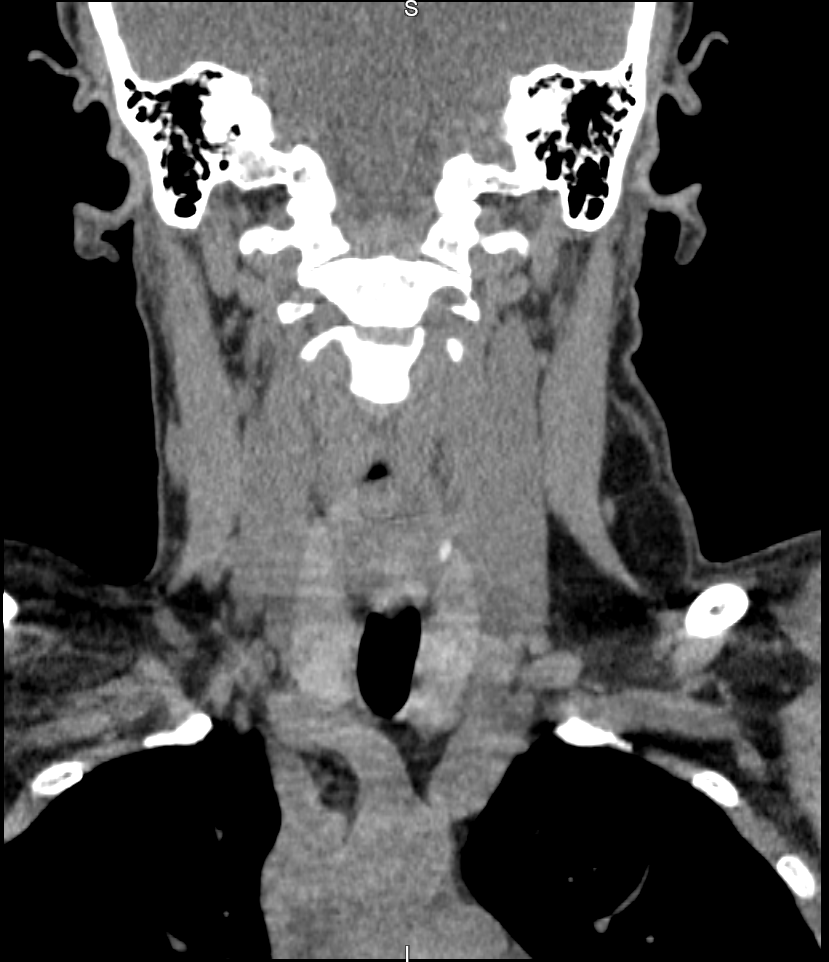

A tomografia do pescoço analisa músculos, vasos, laringe, glândulas salivares, tireóide e linfonodos, nódulos, aumento de volume, estenose de laringe, abscessos, pesquisa de linfonodos e tumores nessa área.